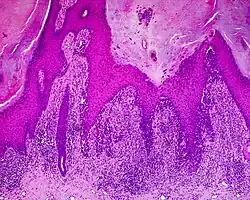

Histología

La principal característica del melanoma lentiginoso acral es la proliferación continua de melanocitos atípicos en la unión dermoepidérmica.[16] Otros signos histológicos del melanoma lentiginoso acral son la invasión dérmica y la desmoplasia.[17]

Según Scolyer et al.,[18] el MLA "suele caracterizarse en su forma más temprana reconocible como melanocitos atípicos únicos dispersos a lo largo de la capa epidérmica de unión".